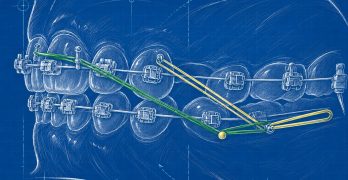

Todo lo que el Ortodoncista necesita saber sobre elásticos

Este artículo llamado Elastics in Orthodontics: A Comprehensive Review y publicado en el International Journal of … [Leer más...] acerca de Todo lo que el Ortodoncista necesita saber sobre elásticos